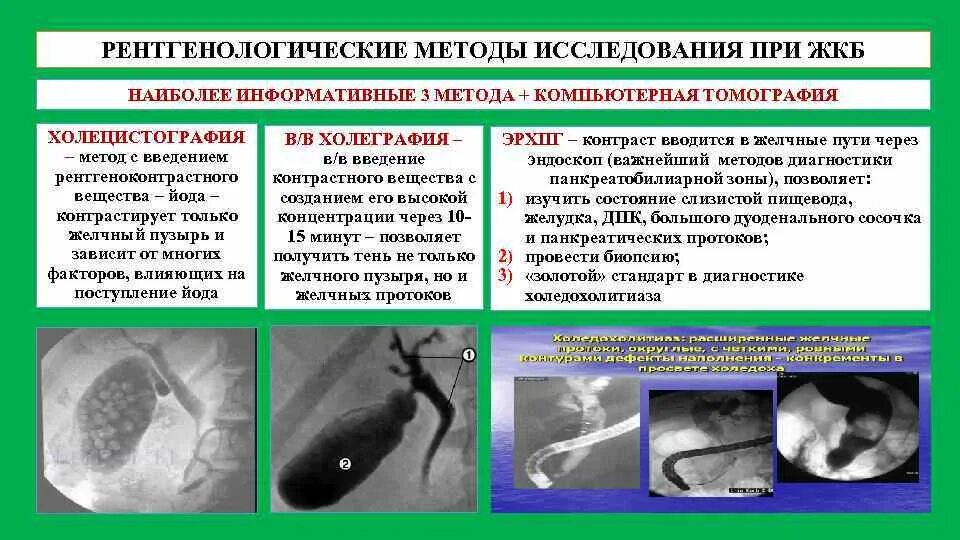

Цирроз печени на мрт с контрастом. Цирроз печени снимки мрт. Цирроз печени снимки кт. Метод диагностики желчекаменной болезни. Методы рентгенологического исследования при желчнокаменной болезни. Рентгенологические методы исследования желчного пузыря. Методы исследования больных с заболеваниями желчного пузыря.

Метод диагностики желчекаменной болезни. Методы рентгенологического исследования при желчнокаменной болезни. Рентгенологические методы исследования желчного пузыря. Методы исследования больных с заболеваниями желчного пузыря. Онкология головного мозга. Раковые заболевания головного мозга.

Проявления поражения теменной доли.. Объемное образование головного мозга. ЭРХПГ при холедохолитиазе заключение. Желчнокаменная болезнь лучевая диагностика. Эндоскопическое исследования механической желтухи. Лучевые исследования при желтухе.

ЭРХПГ при холедохолитиазе заключение. Желчнокаменная болезнь лучевая диагностика. Эндоскопическое исследования механической желтухи. Лучевые исследования при желтухе. Позитронно-эмиссионная томография мозга. ПЭТ кт головного мозга. ПЭТ кт опухоли головного мозга. Позитронно-эмиссионная томография опухоли.